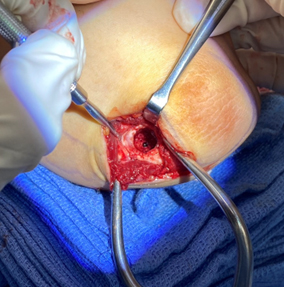

- Large unstable lesions in skeletally immature elbows are indicated for osteochondral autograft transplantation where cartilage can be harvested from a donor site (typically knee) and transferred to elbow lesion to restore normal healthy cartilage

A size-matched plug of cartilage is harvested from the non-weightbearing portion of the knee and prepared for transfer to the elbow

The cartilage plug is contoured and placed within the elbow defect completing the cartilage transfer